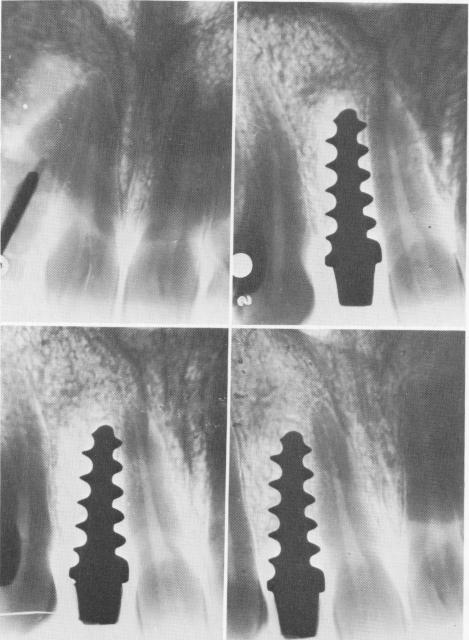

In still another case, done in 1938, a single tooth implant was inserted into the socket of an upper left lateral. As late as 1955, 17 years later, the implant was still functioning (Fig. 5-10).$

Fig. 5-10. A to C, In 1938 an upper left lateral tooth was replaced by an implant inserted by the Strocks. D, Taken in 1951, shows the implant still in place. (Courtesy A. E. Struck.)